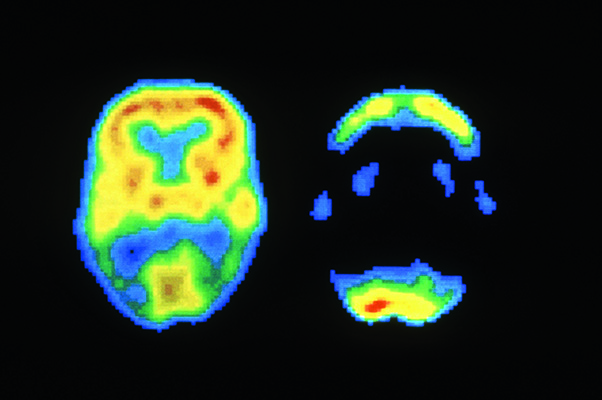

正常大脑(左)和阿尔茨海默病患者的大脑(右)在PET成像时的对比。

在PET成像时,受试者会摄入或被注入痕量放射性材料,以此产生关于新陈代谢、内循环或其他细胞级活动的三维图像。这项研究的共同作者、旧金山分校的放射科医生孙载皓(Jae Ho Sohn)说,人工智能非常适合用于PET,因为在阿尔茨海默病造成神经组织退化前数年,大脑的新陈代谢就已经发生了细微的变化,而神经科医生很难发现这些变化。